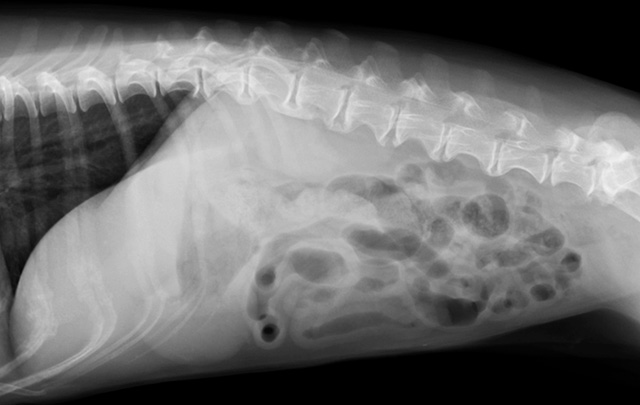

犬・猫は、おもちゃや家族の持ち物、中毒を起こす食べ物など、誤って食べることがあります。物によっては、体の中から傷つけたり、腸を詰まらせたり、毒となって害を及ぼすことがあり、時に緊急の対応が必要なこともあります。当院では、食べたものがどこにあるのかレントゲン検査やエコー検査で確認します。また、動物への負担と今後のリスクをしっかり判断して、催吐処置や内視鏡、摘出手術などの必要な処置を行います。

猫は様々なものを誤って飲み込むことがあります。その中で、大きな塊や紐状の異物(毛糸など)は腸をつまらせることもあり、時に緊急対応が必要なことがあります。特に紐状の異物は、他の異物より腸に穴が開くことが多く、より早い対応が必要になります。当院では、レントゲン検査とエコー検査で異物を早期に診断し、必要な外科摘出をなるべく早いタイミングで適切に行うことで、動物への負担を最小限にします。